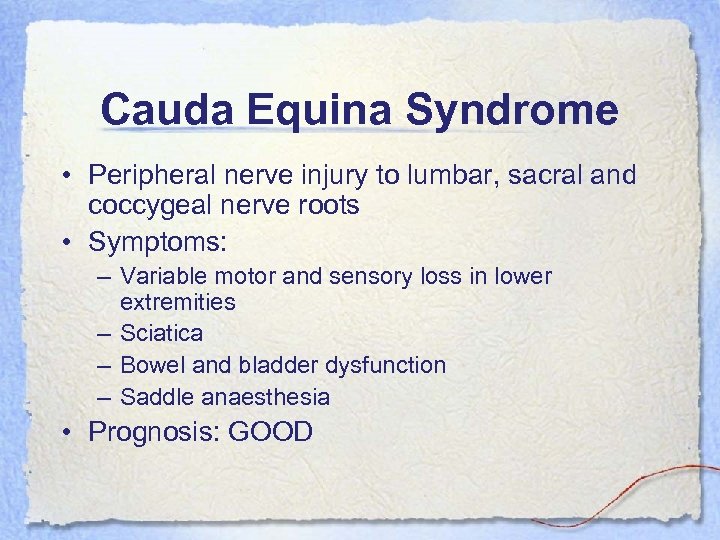

Cauda Equina Syndrome • Peripheral nerve injury to lumbar, sacral and coccygeal nerve roots • Symptoms: – Variable motor and sensory loss in lower extremities – Sciatica – Bowel and bladder dysfunction – Saddle anaesthesia • Prognosis: GOOD

Cauda Equina Syndrome • Peripheral nerve injury to lumbar, sacral and coccygeal nerve roots • Symptoms: – Variable motor and sensory loss in lower extremities – Sciatica – Bowel and bladder dysfunction – Saddle anaesthesia • Prognosis: GOOD